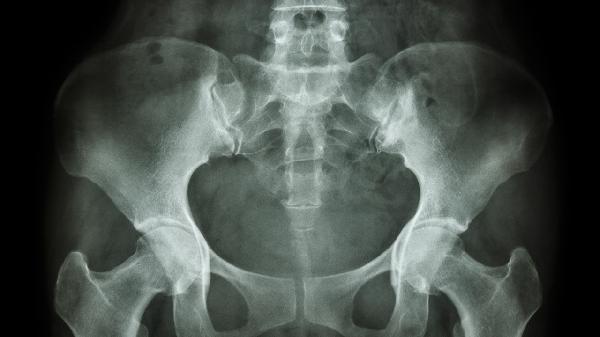

骨盆酸痛可能由妊娠生理变化、久坐劳损、骨质疏松、盆腔炎、腰椎间盘突出症等原因引起,可通过热敷理疗、药物镇痛、抗感染治疗、骨科干预等方式缓解。

绝经后女性或长期服用糖皮质激素者易出现骨盆骨量减少,表现为夜间钝痛或负重时锐痛,可能伴随身高缩短。确诊需进行骨密度检查,治疗需遵医嘱使用阿仑膦酸钠片、碳酸钙D3片等药物,同时补充维生素D并预防跌倒。

L4-L5或L5-S1节段椎间盘突出可能压迫神经根,引起骨盆放射痛并向下肢扩散,咳嗽时疼痛加重。磁共振检查可明确诊断,轻症可用塞来昔布胶囊缓解炎症,重症需考虑椎间孔镜髓核摘除术等微创治疗。